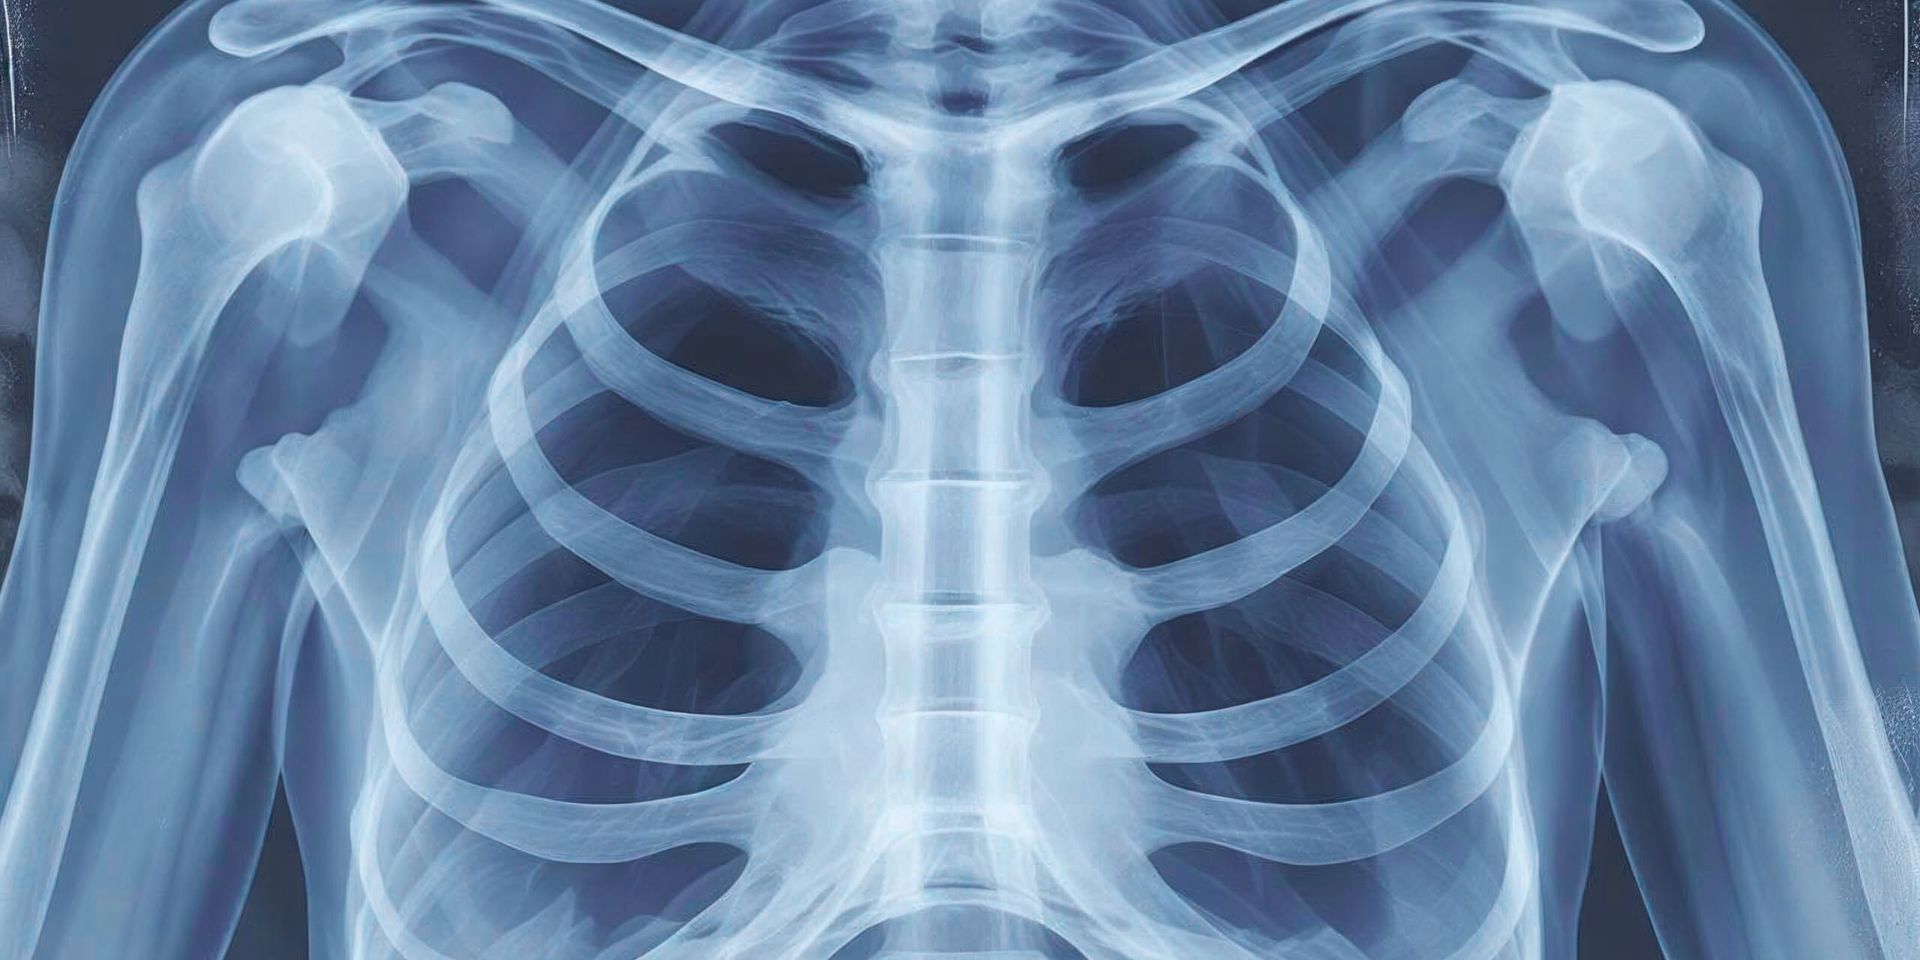

Xrays are typical in initial evaluations. Xrays give a look at the structure of the spine. Xrays reveal any structural abnormalities that the doctor may need to consider. They are simple, but most helpful.

Xrays are windows into the spine's structure and advanced imaging studies such as MRI and CT are doors leading to the inner workings of the spine. Both have their place in your care, but their place is alongside the clinical examination, not in place of it. The role of advanced imaging studies should confirm the clinical examination's diagnosis, not make the diagnosis alone.